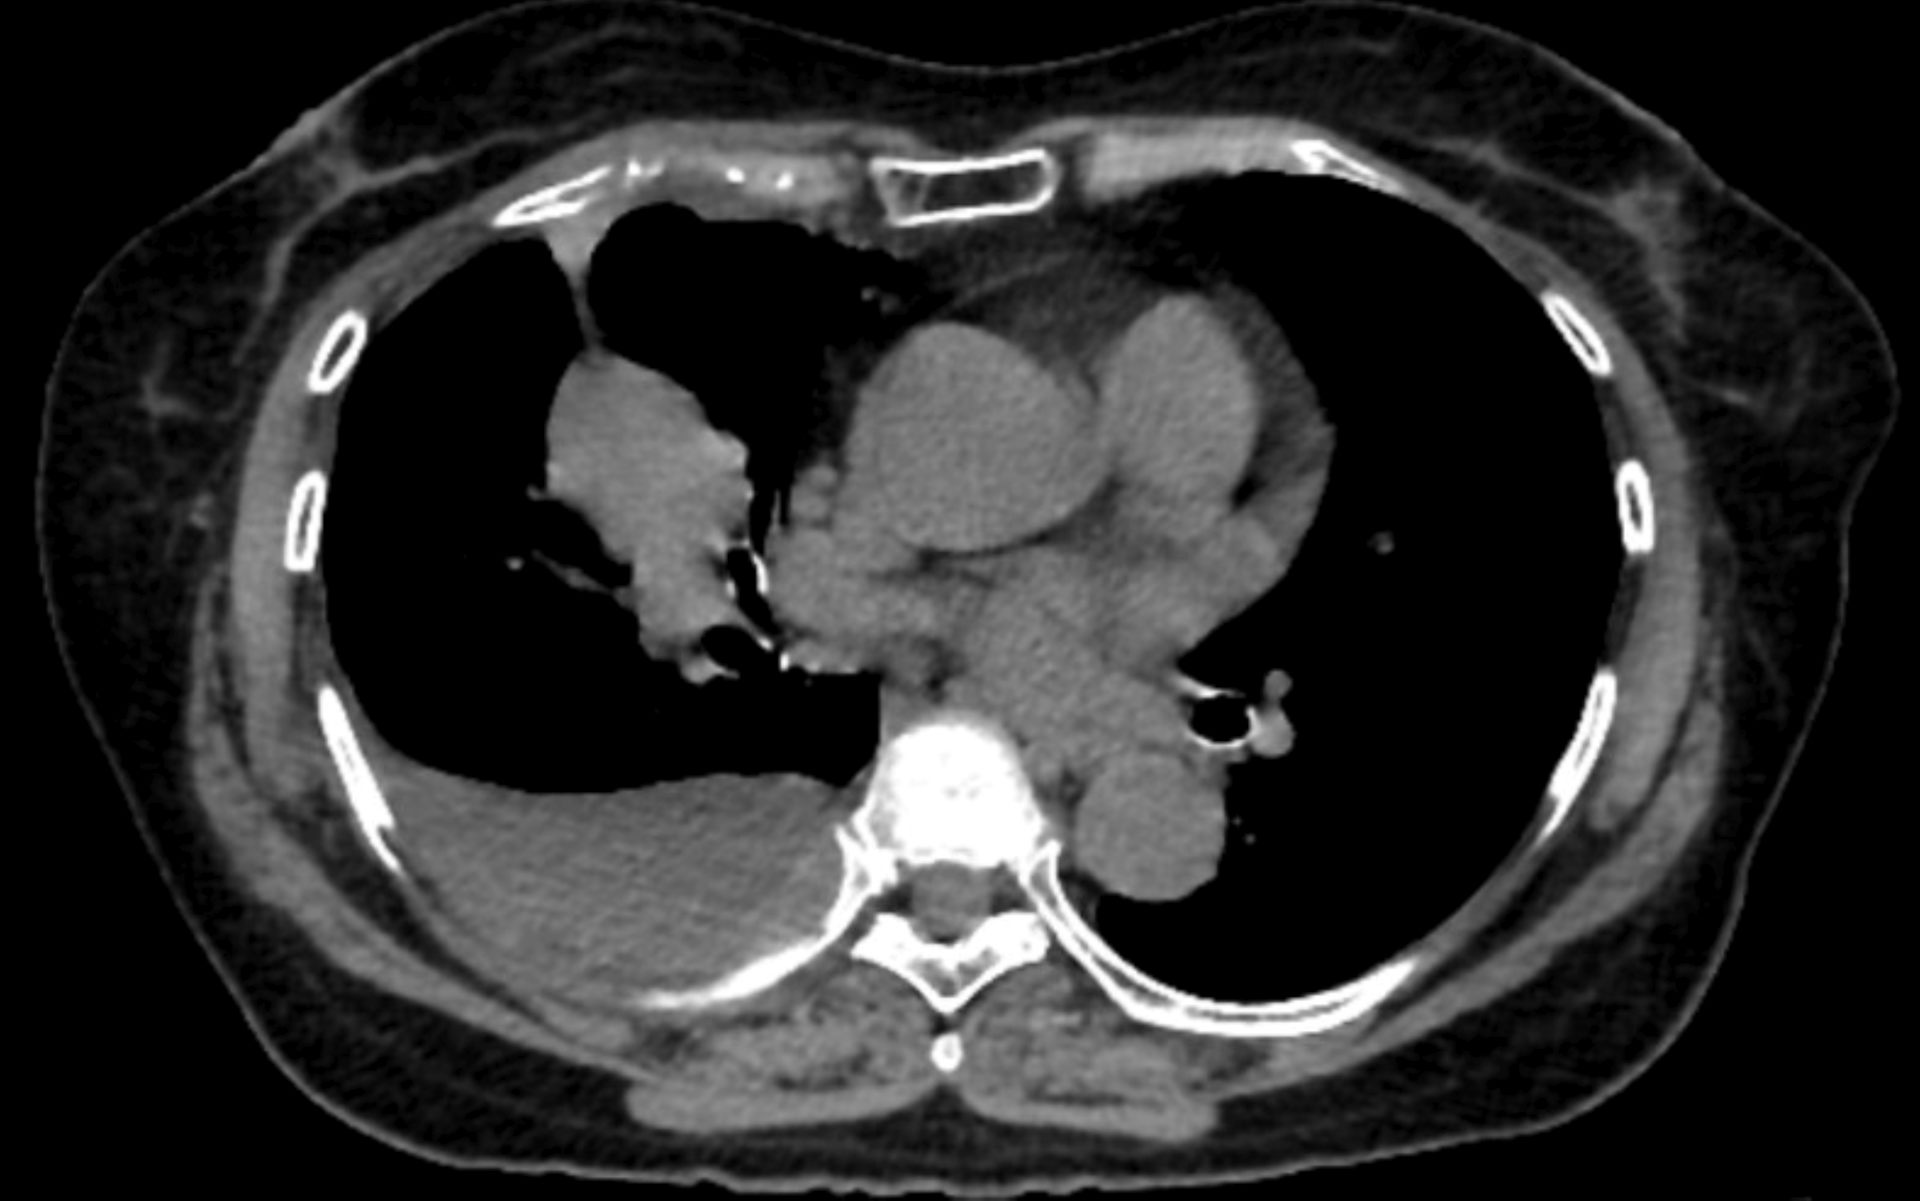

Recently, a patient came to the hospital where I work with a persistent cough. Their doctor had ordered a CT scan – a type of imaging that creates detailed cross-sectional pictures of the body’s interior – to look for pneumonia or another infection.

The scan ruled that out, but it also showed something unexpected: calcium buildup in the walls of the coronary arteries. That finding had nothing to do with the cough, but it pointed toward a much more serious problem. After weighing other risk factors, the patient and their doctor decided to start medication to reduce the risk of a heart attack.

A single chest CT produces hundreds of cross-sectional images. Within those images, a trained eye – or an increasingly capable algorithm – can see calcium accumulating in coronary arteries, assess the condition of the muscles along the spine, estimate bone density and detect early changes in the liver. None of this requires an extra scan, radiation or appointment. The information is already there.

Coronary artery calcium, or CAC, is probably the best demonstration of what opportunistic screening can accomplish. When calcium builds up in the walls of the coronary arteries, it reflects underlying atherosclerosis, the disease process behind most heart attacks. CAC scoring is one of the strongest predictors of future heart attacks, and it adds predictive information beyond what traditional risk calculators provide.

Dedicated cardiac CT scans can measure this calcium precisely. So can a standard lung cancer screening CT, if someone takes the time to look. Studies have found that calcium measurements from lung screening CTs agree closely with those from dedicated cardiac scans, meaning the information is there even when the scan was not designed for cardiac evaluation.

That overlap matters because roughly 19 million noncardiac chest CTs are performed each year in the United States. Every one of those scans passes through the heart. The presence of calcium is visible in the images – yet studies find that when CAC is present, radiologists report it in fewer than half of cases.